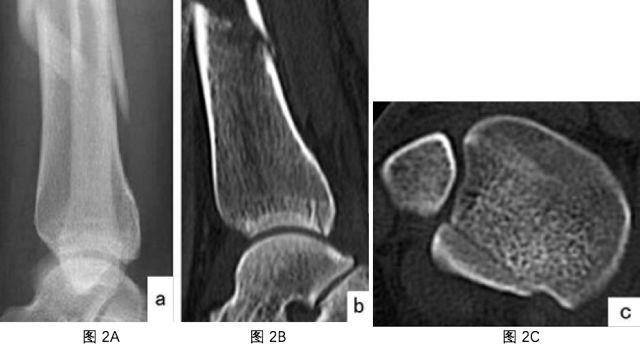

90岁股骨远端长螺旋形骨折